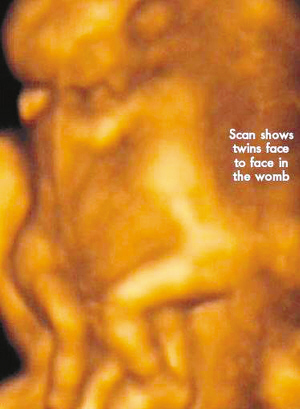

今年初,懷孕7周多的麗莎檢查發(fā)現(xiàn),懷上的竟是一對(duì)腹部緊緊相連的連體男嬰。這對(duì)連體嬰共享一只肝臟,雖然他們擁有各自的心臟,但兩顆心臟卻粘連在了一起。醫(yī)生建議麗莎立即接受流產(chǎn)手術(shù),他認(rèn)為麗莎腹中的連體嬰甚至無法活到她懷孕10周的時(shí)候。

麗莎每周都要到醫(yī)院接受醫(yī)學(xué)掃描,而她腹中的連體嬰也讓醫(yī)生感到驚訝不已,因?yàn)樗麄円呀?jīng)打破了醫(yī)生的死亡預(yù)言,一直在母親子宮中堅(jiān)強(qiáng)活到了現(xiàn)在。麗莎將于兩周內(nèi)接受剖腹產(chǎn)手術(shù)。